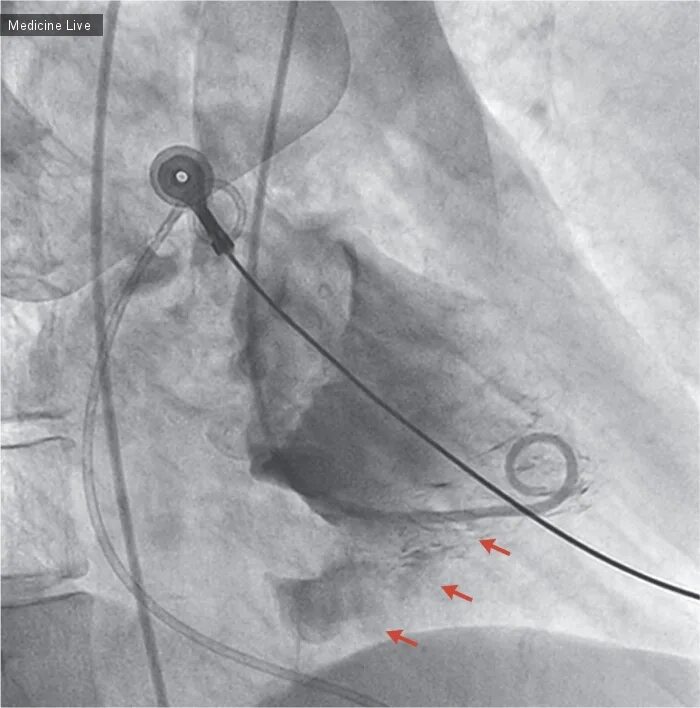

Разрыв 30